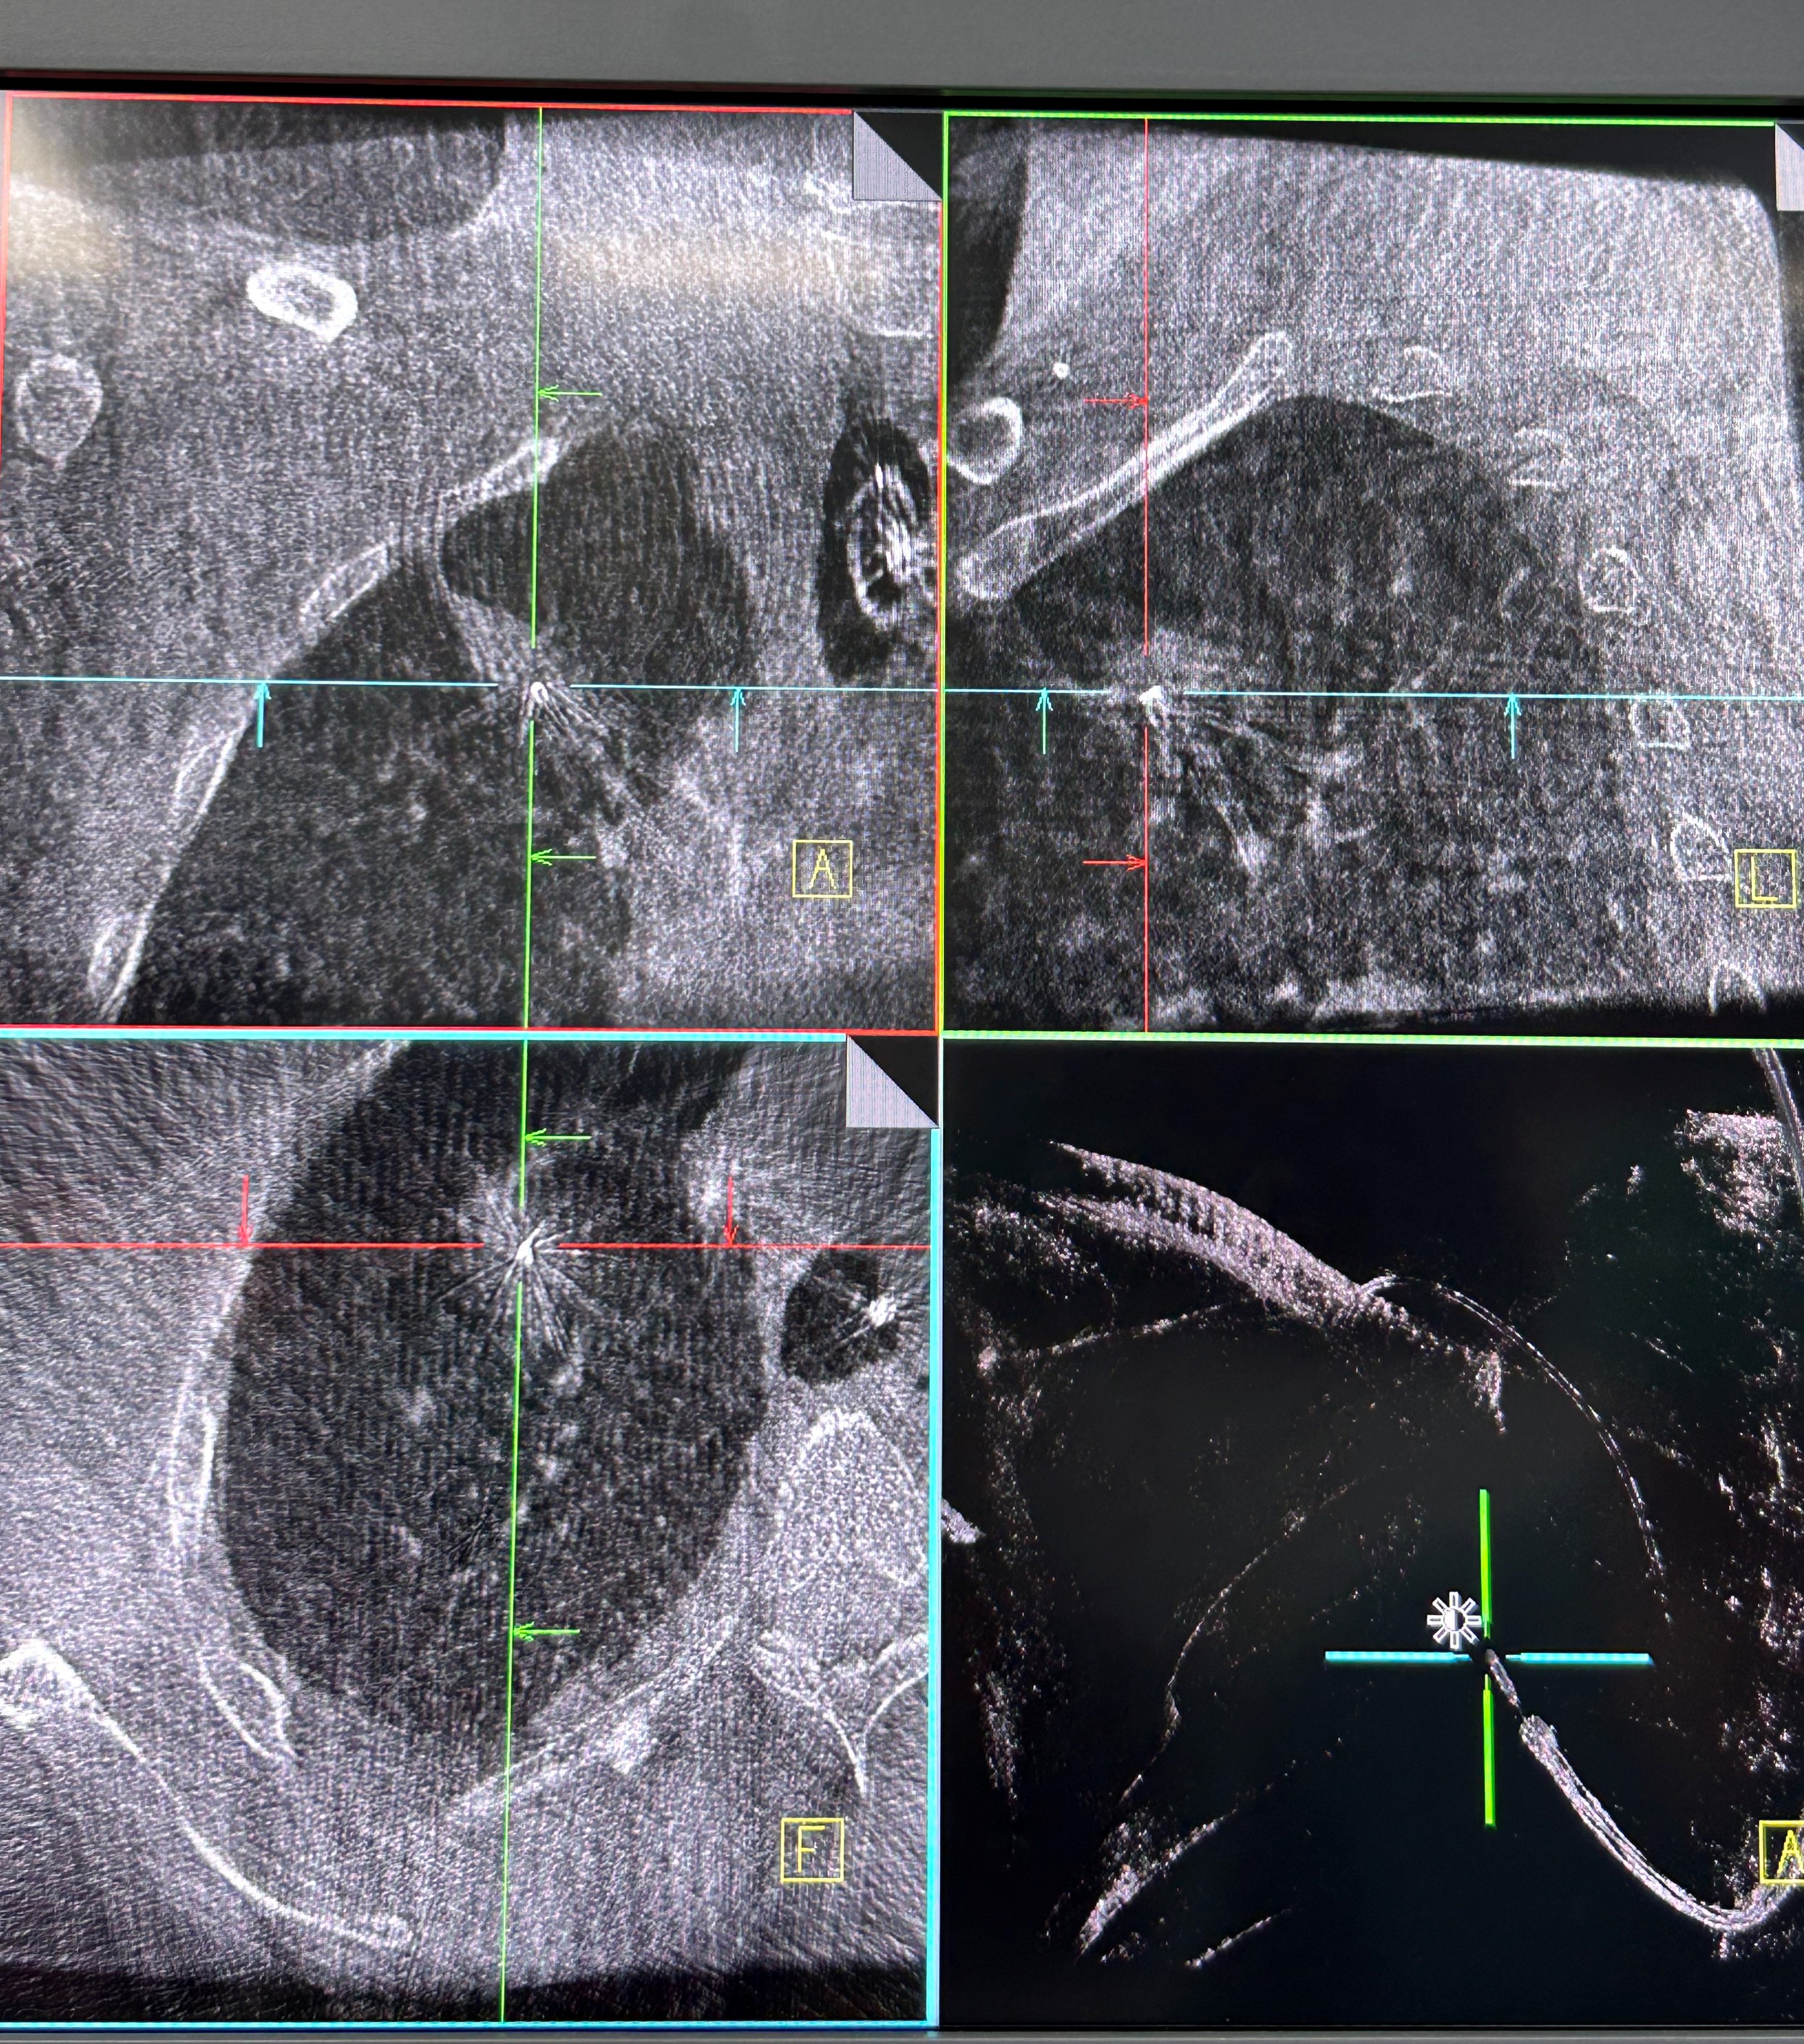

手术当日,呼吸科团队帮助患者在全麻下完成气管插管,手术由蒋军红主任指导,负责手术方案的实时优化与安全保障。曾大雄主任医师和王兰主任医师精准操作机器人支气管镜,在支气管镜导航机器人的精准引导下,通过AI三维重建、智能路径规划以及多模态信息融合,将支气管镜精准“引导”至右上叶尖段病灶处。随后,团队启动CBCT(锥形束计算机断层扫描)通过实时影像复核确认靶病灶,实现病灶“毫米级”精准锁定,彻底解决肺部病灶“找不到、找不准”的核心难题。机器人气管镜导航技术实现了从术前规划到术中操作全流程的智能精准控制,真正做到了肺部病灶的精准覆盖。

明确肿瘤诊断后,治疗方案即刻启动。团队经导航引导鞘管,精准插入一次性冷冻消融针(直径仅1.9mm)。再次通过CBCT确认消融针完全“扎根”于右上叶尖段病灶内后,开启冷冻治疗模式:以-160℃深低温冷冻10分钟、复温至45℃维持3分钟为一个治疗循环。完成了3次循环后,为确保病灶无遗漏,团队微调消融针位置,再次追加2次循环治疗。术后复查CBCT显示,病灶已呈现典型的冷冻后改变,术后两天复查胸部CT提示消融范围满意,治疗效果完全达到预期。整个手术过程中,患者生命体征始终平稳,术后第二天即可下床活动,真正实现了“微创治疗、快速恢复”的目标。